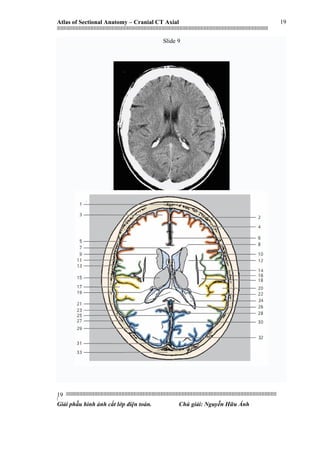

Slide 9

1. Frontal bone

2. Falx cerebri

3. Superior frontal gyrus

4. Middle frontal gyrus

5. Inferior frontal gyrus

6. Cingulate gyrus

7. Corpus callosum (trunk)

8. Lateral ventricle (anteriorhorn)

9. Caudate nucleus (head)

10. Precentral gyrus

11. Central sulcus

12. Corona radiata

13. Postcentral gyrus

14. Claustrum

15. Thalamus

16. Lateral sulcus

17. Temporal operculum

18. Insula

19. Caudatenucleus (tail)

20. Superiortemporal gyrus

21. Corpuscallosum (splenium)

22. Fornix

23. Cingulum

24. Lateral ventricle (collateral trigone,

choroidplexus)

25. Straight sinus

26. Greatcerebral vein (vein of Galen)

27. Parietal bone

28. Parieto-occipital sulcus

29. Occipital gyri

30. Cuneus

31. Superior sagittal sinus

32. Striate cortex

33. Occipital bone

1. Xương trán

2. Liềm não

3. Hồi trán trên

4. Hồi trán giữa

5. Hồi trán dưới

6. Hồi trai (hồi viền)

7. Thân thể trai

8. Sừng trước não thất bên

9. Đầu nhân đuôi

10. Hồi trước trung tâm

11. Rãnh trung tâm

12. Vành tia

13. Hồi sau trung tâm

14. Nhân trước tường

15. Đồi thị

16. Rãnh bên

17. Nắp thái dương *

18. Thuỳ đảo

19. Đuôi nhân đuôi

20. Hồi trên thái dương

21. Lồi thể trai

22. Thể tam giác (cấu trúc hình vòm)

23. Bó liên hợp khứu-hải mã *

24. Đám rối mạch mạc tam giác bên não thất

bên

25. Xoang thẳng

26. Tĩnh mạch não lớn (Tĩnh mạch Galen)

27. Xương đỉnh

28. Rãnh đỉnh chẩm

29. Hồi chẩm

30. Hồi chêm

31. Xoang dọc trên

32. Võ thể vân

33. Xương chẩm

The cingulum is described from various brain images as a C shaped structure within the brain that wraps around

the frontal lobe to the temporal lobe right above the corpus callosum. It is located beneath the cingulate

gyrus within the medial surface of the brain therefore encircling the entire brain. There are two primary parts of

the cingulate cortex, as is typical with most brain structures. There is the posterior cingulate and anterior

cingulate. The anterior is linked to emotion, especially apathyand depression. Here function and structure

changes are related meaning any change within this structure would lead to a function change, particularly

behavioral because of its function involving emotions. Damage to this area can have various effects on mental

disorders and mental health. The posterior section is more related to cognitive functions. This can include

attention, visual and spatial skills, working memory and general memory. Because of its location, the cingulum

is very important to brain structure connectivity and the integration of information that it receives.